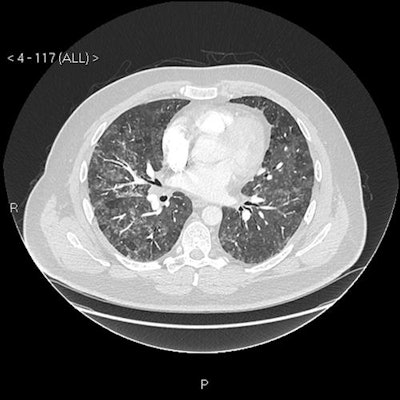

Imaging findings

"Our patient's CXR [chest x-ray] report was initially reported as normal (although we disagreed)," the authors wrote. "He subsequently had a CT pulmonary angiogram with high-resolution reconstruction (to exclude pulmonary thromboembolic as well as interstitial lung disease), reported as showing a ground glass, mosaic pattern in both lungs, with borderline enlarged hilar nodes, presumed reactive."